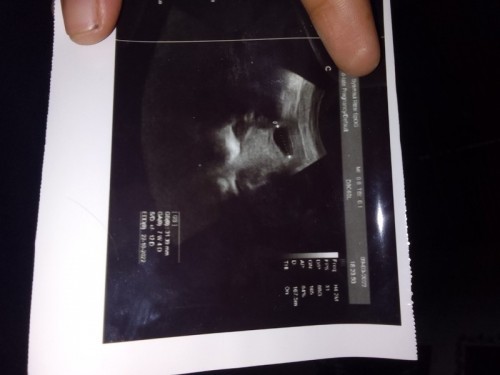

Assalamualaikum bunda . Mudah mudahan pertanyaan saya di jawab ya bun dan jangan meghakimi komentar nya . Bun saya kan kemarin pendarahan lumayan banyak usia kehamilan saya 7 week 5 day dihitung dengan hari ini . Setelah pendarahan saya di bawa kakak ipar saya ke bidan bun 2 kali ke bidan kirain ada penanganan ternyata bidan gk berani ambil resiko karena gk tau keadaan janin di dalam gimana . jadi saya putuskan buat usg . Jadi dari sore smpai malam saya ngantri usg di dokter spog sambil nahan perut yang naudzubillah sakit nya dan saya sampai netes air mata naham nya karena malu org rame saya taha tapi ketika sakit kali netes juga pelan pelan air mata saya bun darah nya udah berhenti tapi sakit nya gak berhenti hun perut kayak di masukin apa gitu di acak2 sakit banget bun ,seteah selesai maghrib saya dapat antrian langsung d suruh masuk . udah masuk dan ush saya kasih tau keluhan saya . dokter bilang gpp itu kantung rahim janin masih ada syaa jelaskan saya masih suka keluar darah neh dok ini pun saya pakai pembalut gpp nnti di rumah yg pnting jgn bnyk gerak dulu atau HB ya dilarang HB dulu 2 minggu lahi kontrol dan dokter ngasih resep obat katanya penguat kandungan posisi saya cuma bwa uang 150.000 bun itu pun di pinjamin kkak ipar jadi nya bun saya gk nebus obat itu tiba tiba tadi malam perut saya kumat sakit nya minta ampun sedikit2 keluar kayak darah merah gelap gitu bun ,terus lendir nanti keluar lagi nanti berhenti sampai sekarang juga hari ini tetap sama perut nya sakit banget bun 😭ya allah bingung banget mau ke rumah sakit gk ada uang soal nya baru pindah rumah dan bpjs msih punya sumatra saya tinghal di aceh kata org bpjs di kantor kalau buat bpjs 1 hari siap tapi untuk aktifkan bpjs itu aktif jya tunggu 14 hari . Otomatis saya harus nunggu 14 hari dulu apa gak bahaya ya bun keluarga lahi sulit ekonomi pulak bun gak kebayang bisa jadi gini mungkin karena saya kecapekan resiko hamil saya pun tidak di ingin kan dokter dan keluarga di karena kan anak pertama lahir di tahun 2019 SC . Anak ke 2 lahir di tahun 2021 SC bahkan masuk ruang icu saya kenak darting sempat koma dan stroke ringan jadi nya hamil ke 3 ini dokter nyaranin buat di kuret kalau emang udah mau keguguran saya antara sayang dan sedih bun saya paling gk tega itu kan termasuk aborsi anak gk bunda 😭😭😭 y allah kesalahan di saya gara2 gak denger keta dokter pakai kontrasepsi spiral saya minum nya pil kb ,karena kata dojter saya pil kb sm suntik gk bakal ngaruh pasti hamil lagi trnyta bener bun #seriusnanya #bantusharing #ingintahu